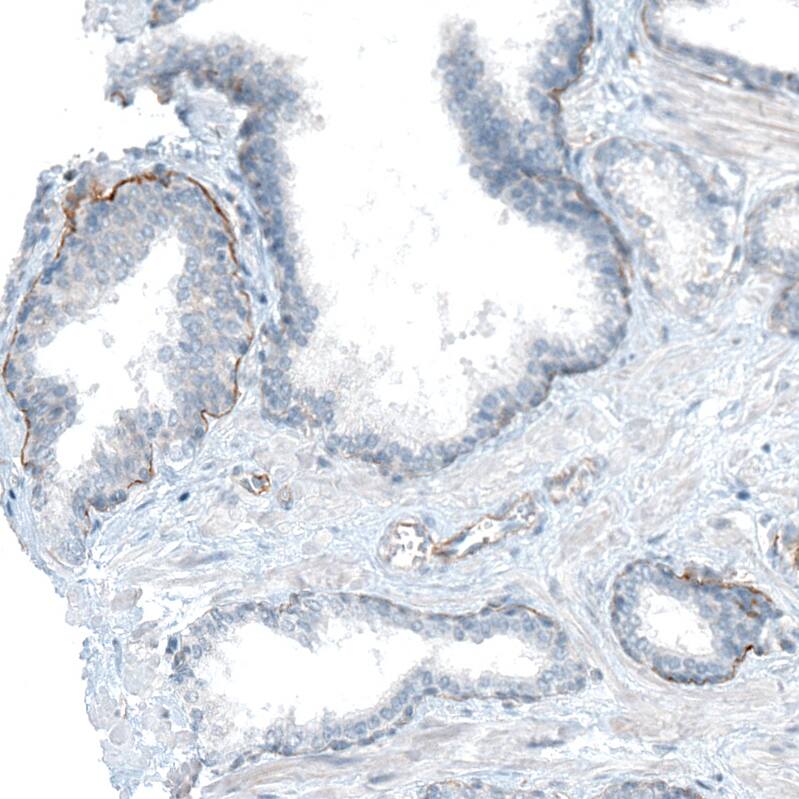

Staining of human prostate shows weak to moderate basement membrane positivity in glandular cells.